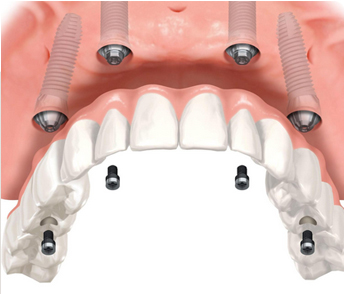

避开重要神经,

减少创伤

无需植骨,

节省时间与费用

突出特点,实现即拔即种即用,结合后能吃能咬

瑞典Nobel种植牙系统是基于计算机引导下的自动设计和激光定位,使得种植牙过程由原来的手工操作转化为自动化处理,变得智能便捷。

采用螺纹设计和表面处理技术,有着与骨相似的生物适应性,增加初期稳定性和自攻性,骨质较差时也能很好结合。

ICX种拥有很高的灵活性,面对长期半颌和全颌重度骨缺损也能理想修复。ICX全颌新的multi全颌修复方案,在短短的1-2小时内即可完成手术,避免了长期复杂的骨移植手术,大大减少了手术创伤,节省了治疗费用。

兼顾美学效果与舒适稳定。圆锥形根状几何结构和双螺纹设计有利于提高骨结合率,保证了良好的初期稳定性,实现即刻负重。